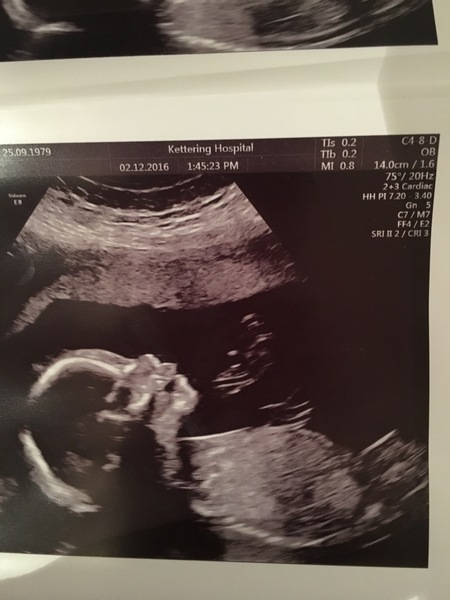

Scan went well, team yellow for us.

Great clear photo RaRa

Rara that is a lovely scan pic, the little upturned nose is so cute!!